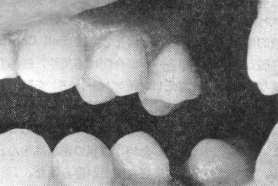

症 例 〔2〕

図.7,8はBridgeへの応用例で患者は,43才の女性で,装着後6ケ月経過した,F6DのGold Bridgeである。

術前は,7に不適合なCrawnが入っており,6はC4で,抜歯する必要があった。

しかし,5は健全歯で骨植も良好な歯牙であるため患者の希望をとり入れ,審美性を考慮して,5の歯質の保護と強い雑持カを求めるためピンインレーを応用したものである.

この場合,ピンばInlayの窩洞の近心に1本形成した。6ケ月を経過した現在もピンの離脱や冷温水痛,歯牙の動揺などの臨床的不快症状はみあたらなかった。又,ロ腔内の清掃状態も良好であった。